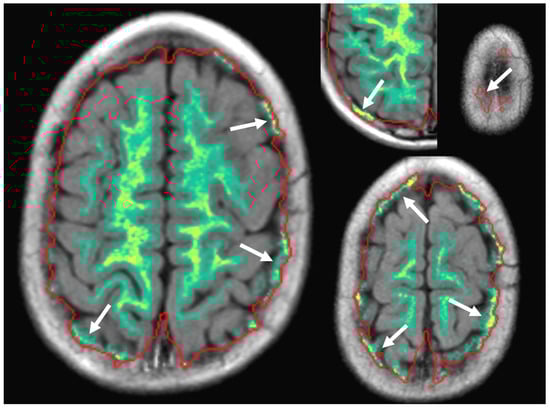

2.2. SyMRI Volume Measurements

2.3. Manual Volume Measurements